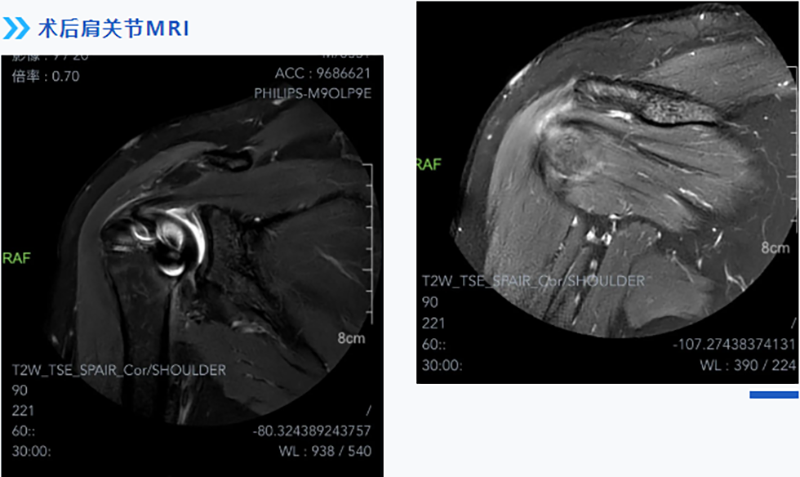

考慮到患者對術后功能期望值較高,術中對于如何將撕裂的肌腱完全恢復如初等因素充滿了挑戰。經過充分的術前準備,運動醫學科團隊應用關節鏡下微創技術,根據術中實際情況,精準植入縫合錨釘,將撕裂的肩袖縫合回原本的位置,恢復其原本具有的功能,被牽拉的腋神經也得到了松解,術后患者患肢疼痛、麻木的癥狀立即得到了緩解。

術后3個月,患者門診復查時,肩關節功能開始逐步恢復,已經能自己抬得起手,肩膀麻木的癥狀也沒有了,患者對治療效果表示非常滿意。

運動醫學科主任韋釗嵐博士介紹,利用關節鏡下微創技術完全保留了肩袖組織的正常神經、血管組織及其感覺功能,使肩袖組織完全解剖復位,恢復其原有的生物力學,增加了患者肩關節的穩定性,促進肩關節本體感覺的恢復。關節鏡下微創技術相較于傳統手術打開關節腔治療的方式,具有切口小、感染率低等優勢,且關節鏡手術可同時治療肩峰撞擊綜合征、關節盂唇撕裂、肩袖疾病、肩關節不穩等多種疾病。